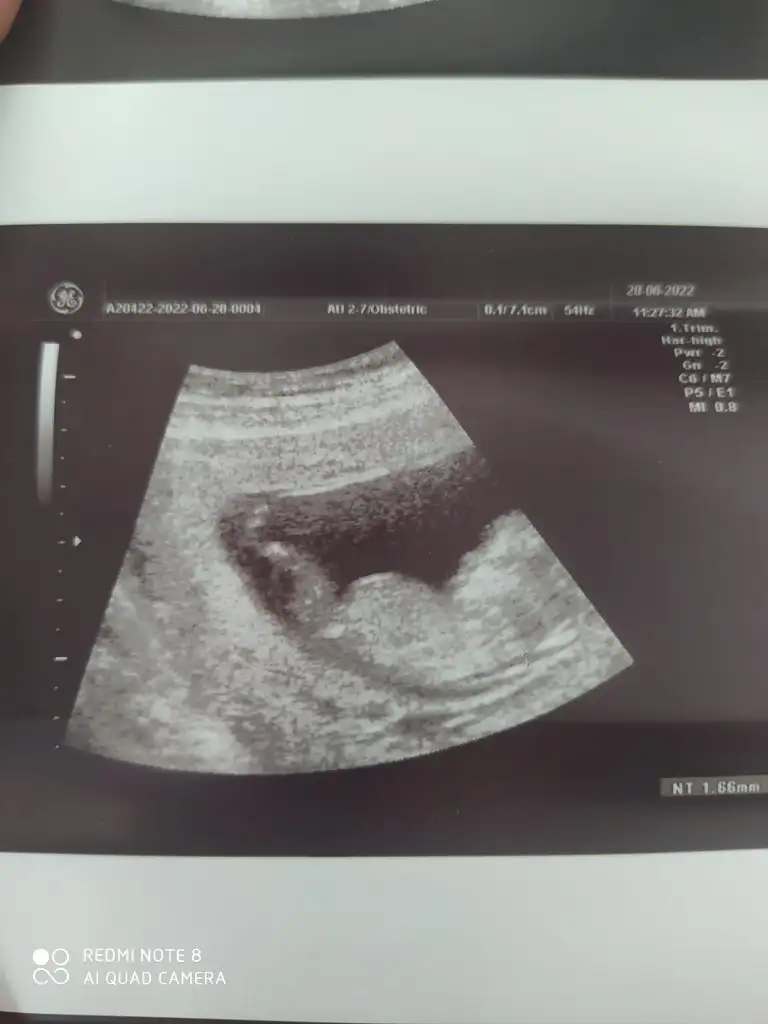

Merhaba 8 haftalık karından bakıldı

Eklentiler

• IMG-20220628-WA0001.webp

IMG-20220628-WA0001.webp

14,9 KB · Görüntüleme: 74